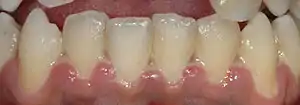

Dentin hypersensitivity

Dentin hypersensitivity is a sharp, short-lasting dental pain occurring in about 15% of the population,[16] which is triggered by cold (such as liquids or air), sweet or spicy foods, and beverages.[17] Teeth will normally have some sensation to these triggers,[18] but what separates hypersensitivity from regular tooth sensation is the intensity of the pain. Hypersensitivity is most commonly caused by a lack of insulation from the triggers in the mouth due to gingival recession (receding gums) exposing the roots of the teeth, although it can occur after scaling and root planing or dental bleaching, or as a result of erosion.[19] The pulp of the tooth remains normal and healthy in dentin hypersensitivity.[10]: 510

Many topical treatments for dentin hypersensitivity are available, including desensitizing toothpastes and protective varnishes that coat the exposed dentin surface.[16] Treatment of the root cause is critical, as topical measures are typically short lasting.[10]: 510 Over time, the pulp usually adapts by producing new layers of dentin inside the pulp chamber called tertiary dentin, increasing the thickness between the pulp and the exposed dentin surface and lessening the hypersensitivity.[10]: 510